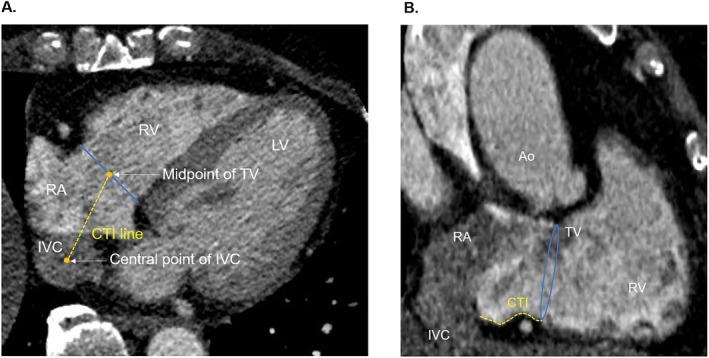

Cryoablation is an alternative to radiofrequency ablation for the treatment of cavotricuspid isthmus (CTI)-dependent atrial flutter (AFL). However, the anatomical features that make achieving a CTI conduction block using cryoablation challenging remain unclear.

冷冻消融是治疗三尖瓣峡部(CTI)依赖性心房扑动(AFL)的一种替代射频消融的方法。然而,使用冷冻消融实现CTI传导阻滞具有挑战性的解剖学特征仍不清楚。

方法

本研究纳入了100例连续接受CTI冷冻消融治疗AFL的患者。患者分为两组:首次通过组,即实现首次通过CTI传导阻滞的患者(n = 72)和非首次通过组,即未实现首次通过CTI传导阻滞的患者(n = 28)。我们分析了首次序贯CTI冷冻消融过程中的解剖学特征和导管温度变化。